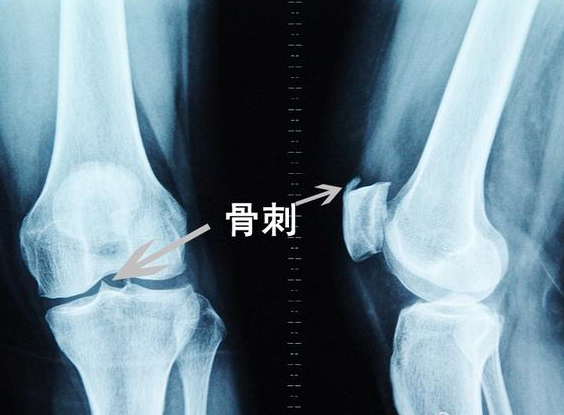

很多病友看到自己的报告上写着骨质增生,心理想我这么年轻就增生了,想尽各种办法想消掉这个刺头。骨刺又称骨赘、骨质增生,是人体对骨附着的韧带、筋膜慢性牵拉性损伤的一种自身保护性反应,也与骨骼、韧带退行性病变有关。骨骼不断进行着新陈代谢,新生和老化处于动态平衡状态。进入中老年,老化速度大于生长速度,则出现骨质疏松,在经常负重的关节上就会长出骨赘。足跟承受的压力最大,最易发生骨刺。膝、髋关节是负重的大关节,也是容易长骨刺的部位。长期睡姿、坐姿不良,缺少运动,以及长期摄取含钙的食物少,常穿高跟鞋等,都是骨刺发生的病因。据统计,50岁以上的人有骨赘的占80%左右,60岁以上占90%左右,而70岁以上有骨赘的就达100%了。

对骨刺不必恐惧。骨刺并非长入骨内的刺,在侧位X线片上是“刺”状,而在正位X线片上一般不显示。因为它有一种自身保护作用,以一般不会疼痛。有些患者出现疼痛,是因为有软组织(韧带、筋膜)损伤或劳损;有的是由于骨骼、软组织退行性病变产生导致疼痛的介质;有的是由于以上原因引起的骨内压增高。在休息时仍然疼痛(医学上称为休息痛),但不是刀割样锐性痛,而是沉闷、钝痛、酸困和说不出的难受,这就是骨内压增高的表现。